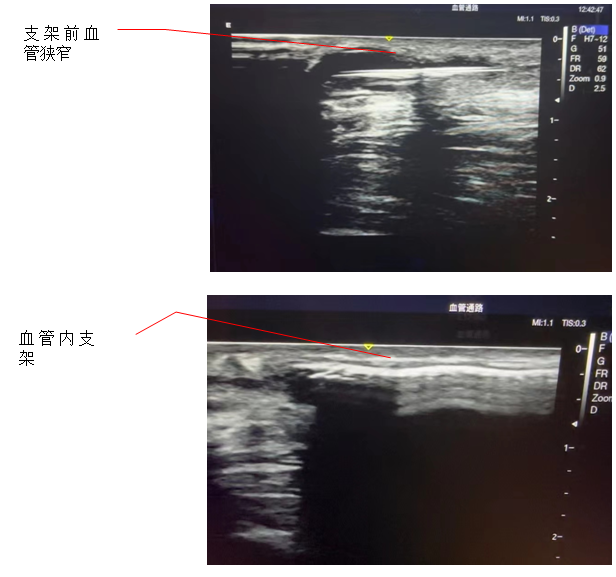

患者为男性,被诊断为慢性肾功能衰竭,使用左前臂人工血管内瘘规律透析1年。患者此前因为人工血管内瘘狭窄曾接受两次经皮静脉球囊扩张术(PTA),但术后狭窄很快复发。内瘘最常见的并发症是狭窄,长期高速的血流会引起血管内膜反应性增生,导致内瘘管腔狭窄和血流量不足。所以,覆膜支架植入术是比较好的解决方法。术后,患者人工血管内瘘血流恢复通畅,透析过程中血流量充足、静脉压正常,达到了较好预期的手术效果。

血液透析通路是尿毒症患者的“生命线”,目前尿毒症患者最常用的透析通路是自体动静脉内瘘和人工血管内瘘。传统的支架植入术是在DSA造影下进行,而超声引导下介入手术是近几年新兴的技术,超声引导具有方便、无辐射损伤、无造影剂损害、可显示闭塞病变等优点,特别适合动静脉内瘘等外周血管的介入治疗。